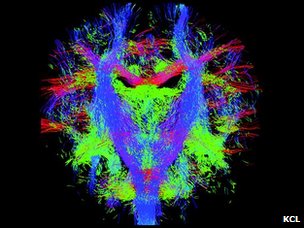

英国科学家开始绘制胎儿脑神经系统路径图,计划6年完成。

这张动态的脑神经路径图可以被用来按图索骥,解读不同的脑神经之间如何沟通、交流和联结的。

伦敦大学国王学院、帝国理工大学和牛津大学附属医院的儿科专家们的制图目标是希望能精确地、动态地图解脑神经信息传递线路和流程,在最细微具体的层次显示脑神经系统的发育成型过程。

新生儿的脑神经纤维束

这项研究的核心是MRI扫描技术的更新,使得科学家得以精确捕捉以前力所难及的胎儿脑神经系统成长的细节。